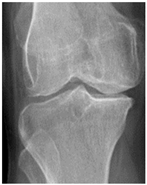

In the local dataset, we have selected 60 adult patient files of men and women with knee disorders who were radiographically examined at the Radiology Department of the El Kelaa des Sraghna Provincial Hospital. Each file consists of one or more knee radiographs in Dicom format as presented in Figure 7. The images were acquired using a standard ITALRAY radiology table. After analysis, 30 images with implants and non-posterior-anterior examination views were excluded and 30 left and right Dicom knees were retained to validate this work. To make the validation local dataset, the ROI was selected manually as illustrated in Figure 8. Then, each patient’s file was presented to a rheumatologist with PNG images. In case of disagreement between our diagnostic system and the rheumatologist, a radiologist was consulted for arbitration to make the final decision.

Figure 7.

Example of knee X-ray images collected and filtered from patients with knee symptoms.